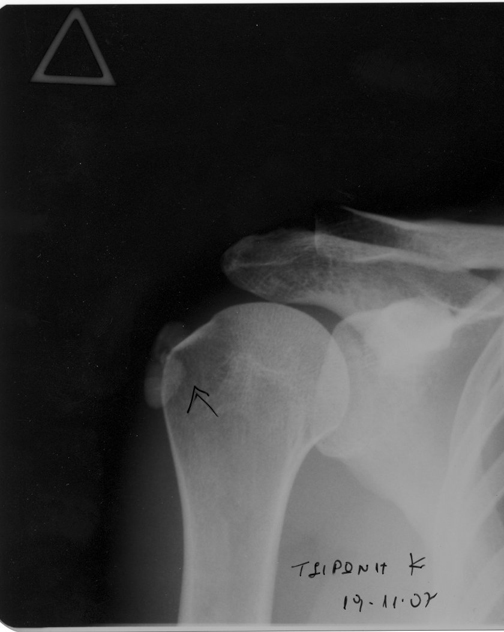

Πριν

Απεικόνιση τενοντίτιδας υπερακανθίου πριν τη θεραπεία:

Απεικόνιση τενοντίτιδας υπερακανθίου πριν τη θεραπεία